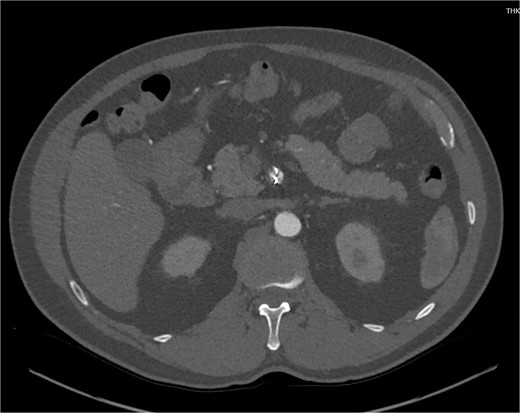

The patient was initially managed conservatively with blood pressure control and anticoagulation using Apixaban and aspirin. However, after one day of treatment, he experienced worsening abdominal pain and a hypertensive crisis with blood pressure reaching 228/113 mmHg. A follow-up CTA showed an extension of the SMA dissection extending into branch vessels, now associated with a small 1 cm aneurysm and hemoperitoneum (Fig. 2). Apixaban was stopped, and the patient was transitioned to a heparin drip, with an esmolol drip as needed for blood pressure control. As his symptoms improved, he was bridged back to apixaban and discharged on enoxaparin.

CTA demonstrating a more extensive SMA dissection extending into branch vessels. New hemoperitoneum most pronounced in the left abdomen with no active extravasation noted but probably arises from the left mesentery.